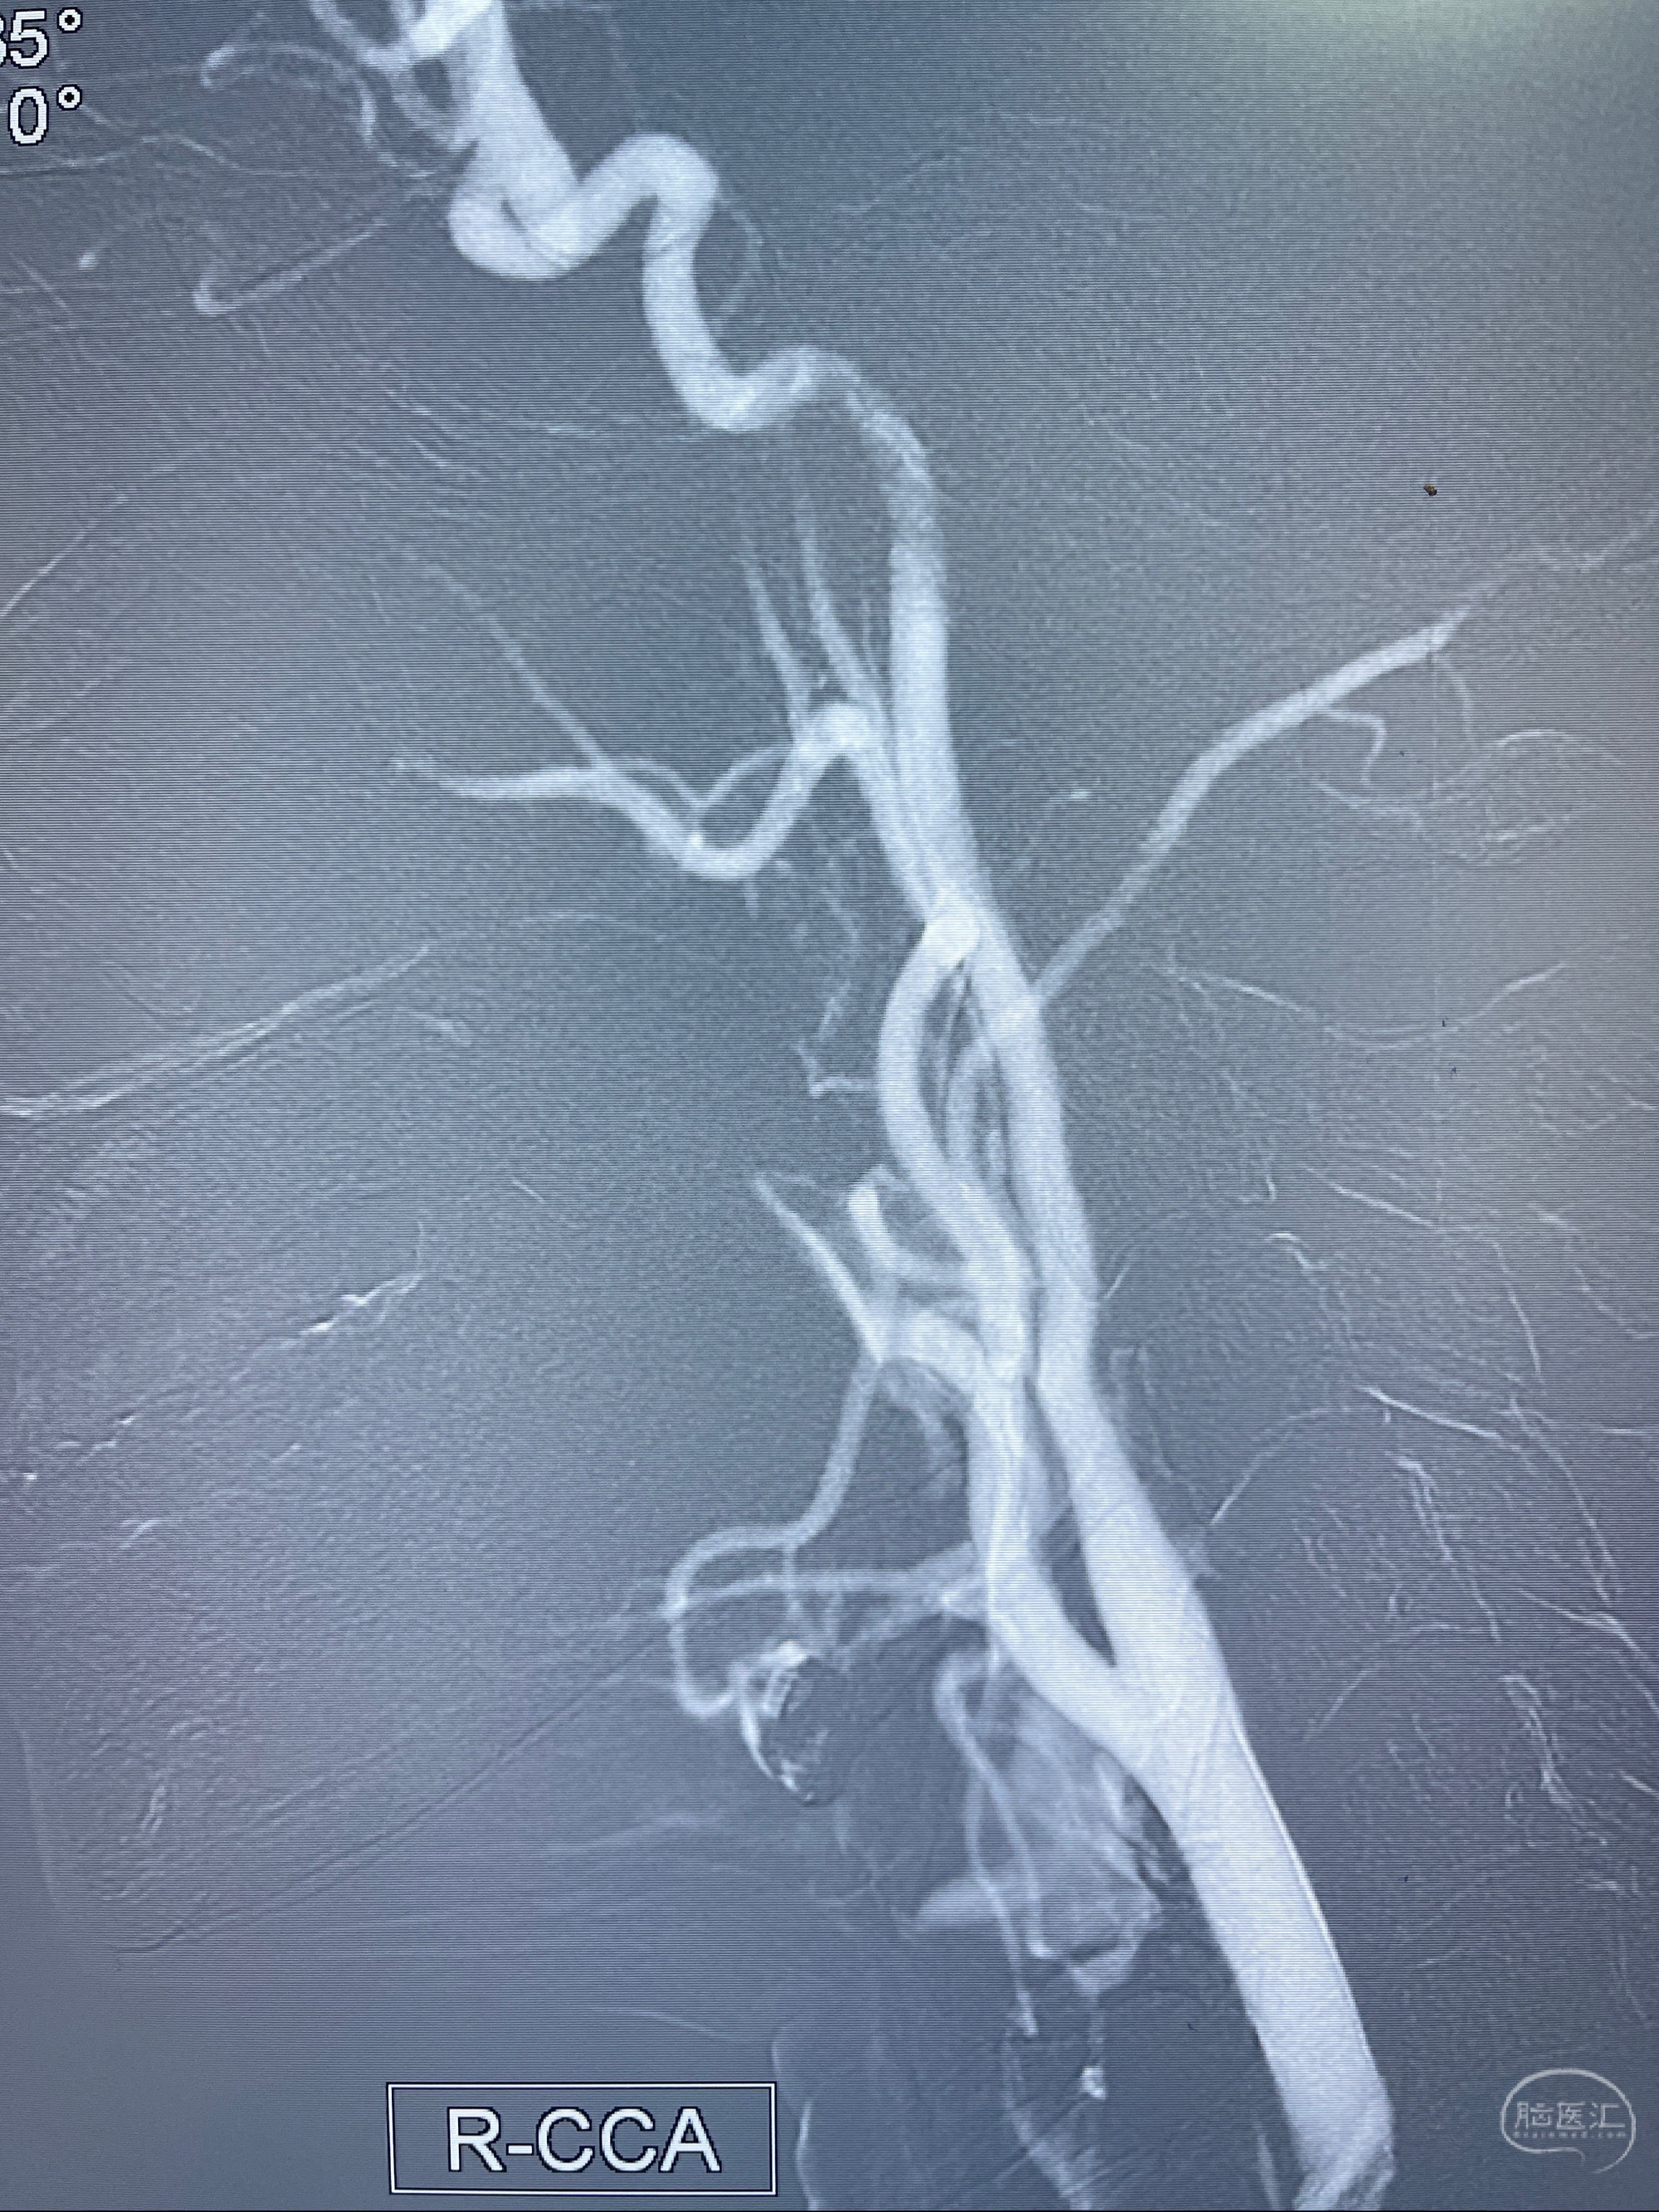

2023-07-27全脑血管造影:双侧颈内动脉眼动脉段动脉瘤,右侧较大

2023-08-01全麻下行双侧颈眼动脉瘤支架辅助栓塞